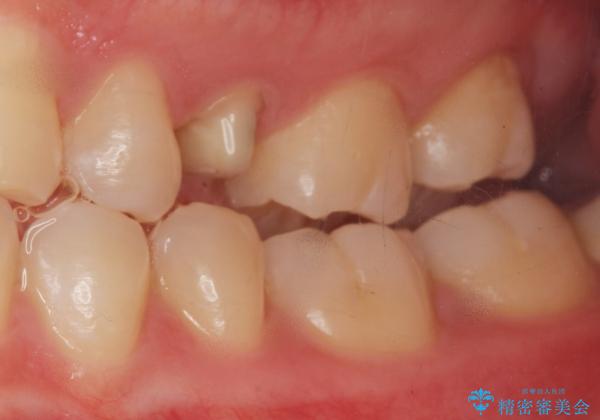

精査したところ、左上の小臼歯(左上5)は被せ物がないまま放置していたことにより、両隣の歯が寄ってきてスペースが少なくなり、また隣の歯(左上4)も虫歯になっていました。

隣の歯の虫歯治療(保険内のレジン充填)後、セラミッククラウンによる補綴を行いました。